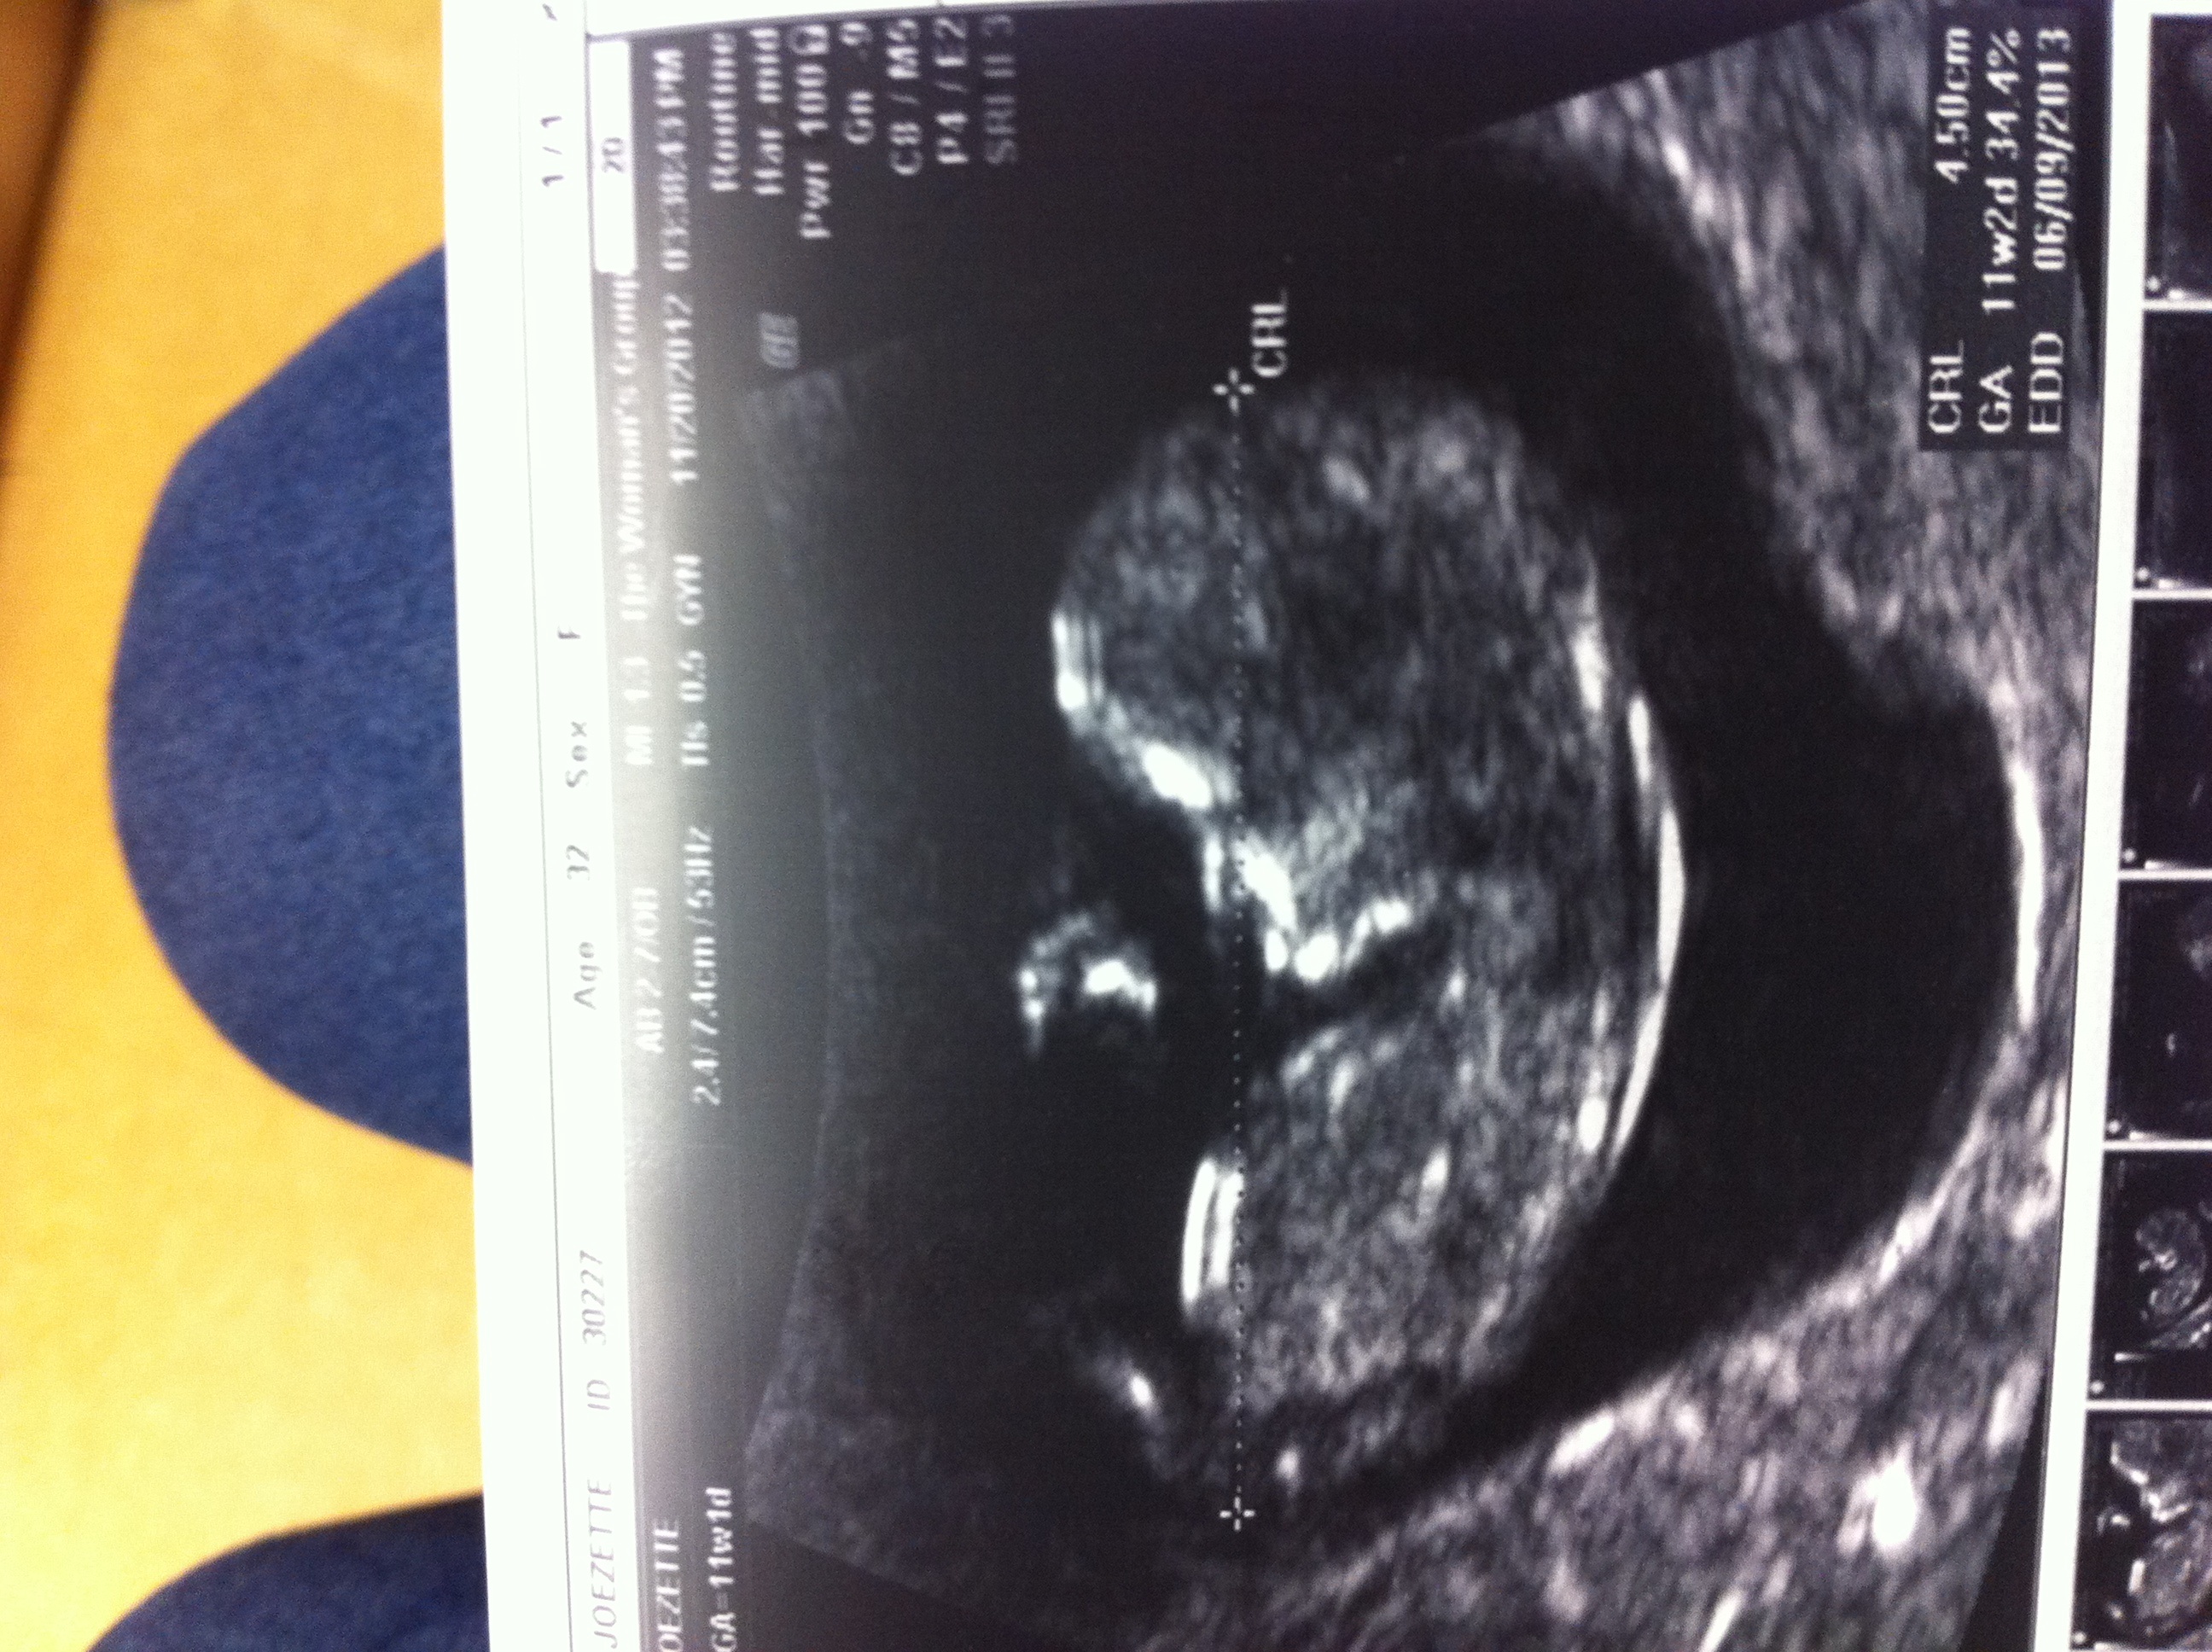

So I'm measuring 11wk 2 day, ultrasound tech wouldn't confirm 100%, but nub theory Attachment 6499was pointing down at 30 degree angle and she said she would lean girl. She thought too early. Here's skull profile, thoughts? Heart rate 166, but my 2 others had 176 & 160.